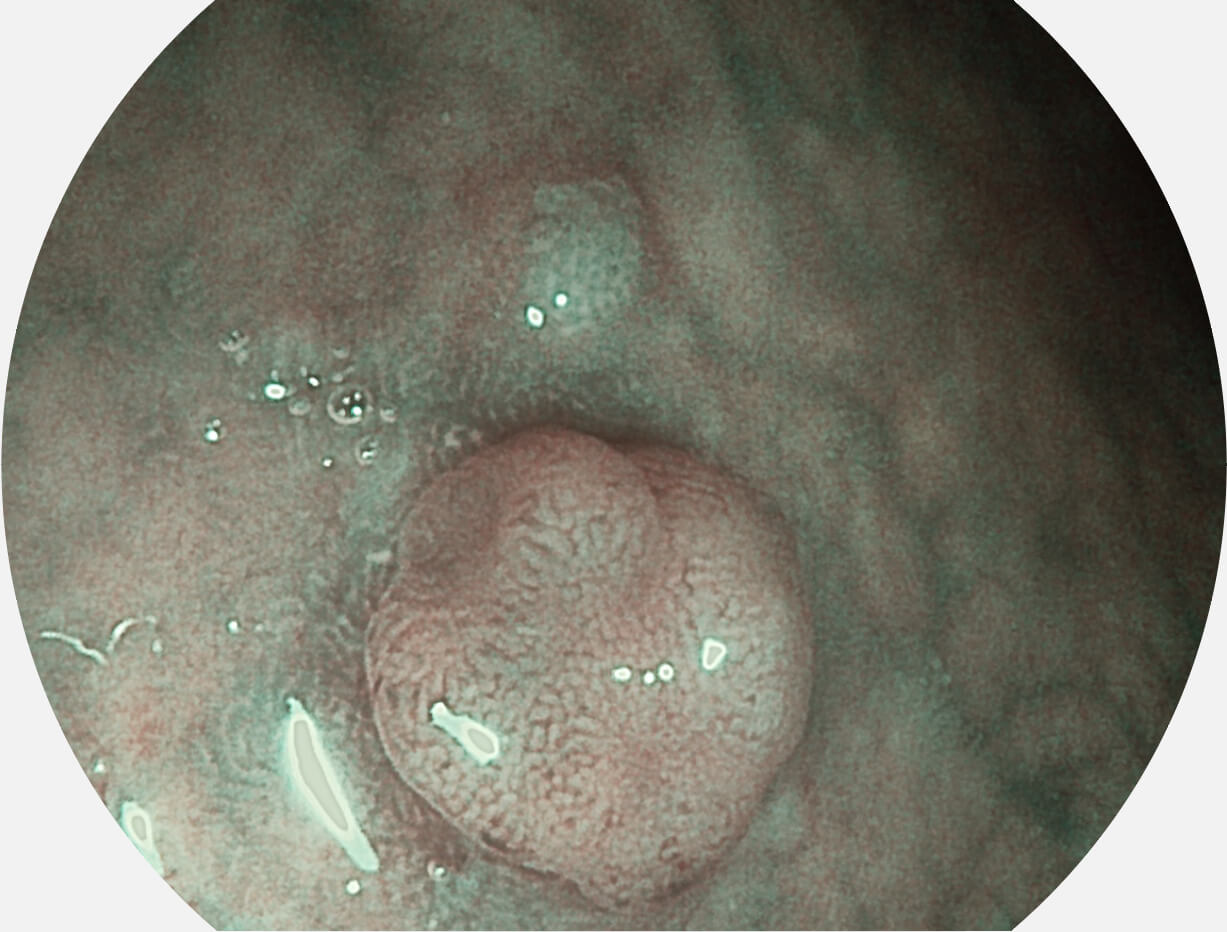

Spectral Focused lmaging, SFI

图像具有高亮度、高黏膜血管颜色对比度的特点,且不改变粘液、食物残渣、粪便的基本颜色,可在中远景下进行观察,助力消化道早期疾病的诊断。

白光图像

SFI图像